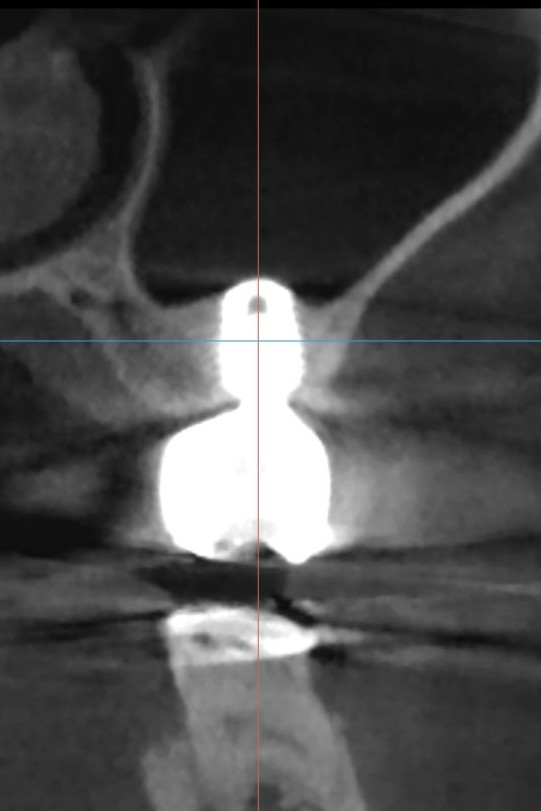

術後3年、CTでのフォローアップ

埋入直後のCTでは、挙上された上顎洞底の骨の写り方はまだ不鮮明です。術後3年で撮影したCTでは、インプラント周囲の明瞭な骨形成が確認され、上顎洞内にも問題を認めず、安定した経過をたどっています。

インプラント埋入直後のCT

術後3年フォローアップCT